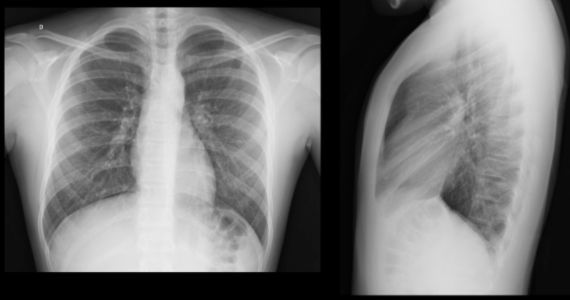

Dona Ana Cláudia, 32 anos, previamente saudável, apresenta história de dor precordial de início há 24 horas, de forte intensidade, a qual piora com a respiração, deglutição e ao se deitar. A dor irradia para o pescoço e ombro (em especial para as bordas do músculo trapézio). Relata que a queixa é constante e não se relaciona com esforço, além de não aliviar com dipirona 500 mg. EF: eupneica, normocorada e afebril. Pressão arterial: 142x82 mmHg, FC: 106 bpm, FR: 15 rpm, temperatura axilar de 37,1ºC e saturação de 95% em ar ambiente. Os marcadores de necrose (0- 6-9 horas) apresentaram discreta elevação. Eletrocardiograma e raios X do tórax, a seguir.

Assinale a alternativa CORRETA para o tratamento inicial proposto para Ana Cláudia.